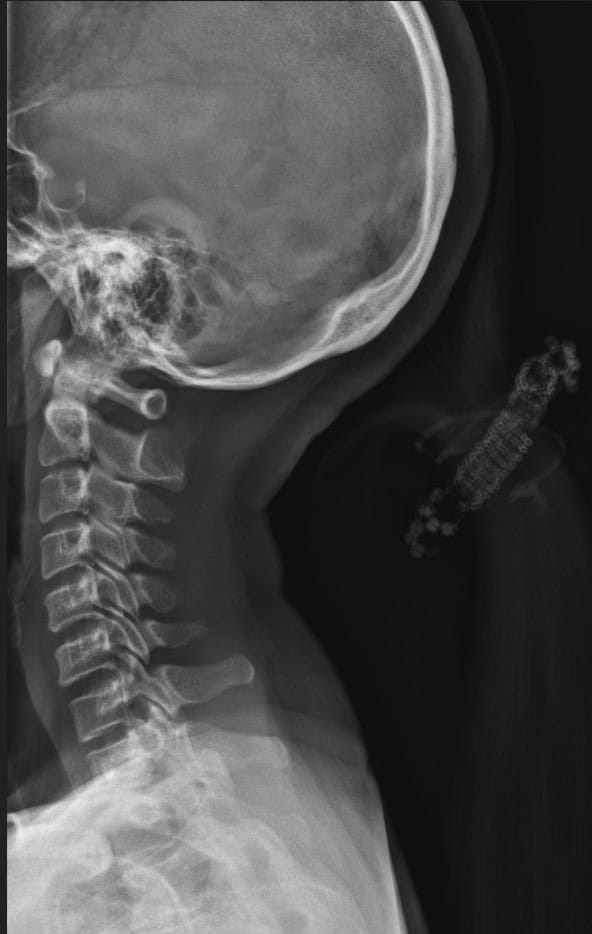

Pre Scan